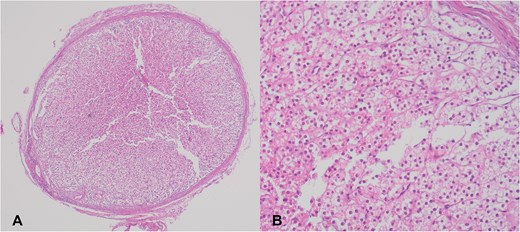

A 35-year-old woman underwent elective surgery for umbilical hernia repair along with cosmetic abdominoplasty and liposuction. Her medical history included two pregnancies, both of which were uncomplicated normal vaginal deliveries. Preoperative abdominal ultrasound and routine blood work were within normal limits. After completing the liposuction, during the herniorrhaphy, the surgeon discovered a small yellowish-tan nodule measuring 4 × 4 mm on the apex of the hernia sac (Fig. 1A). After liposuction, the abdominal flap was elevated with deeper dissection over the rectus abdominis aponeurosis. Then, the umbilicus was freed, and diastasis repair was performed. Afterward, the repair of the umbilical hernia was successfully completed. The nodule within the hernia sac was resected and sent for pathological examination. Following this, the abdominoplasty was performed. The patient was discharged without complications after a 1-day stay in the hospital. Pathology results indicated the presence of an encapsulated nodule (Fig. 1A) consisting adrenal cortical tissue within the hernia sac, composed of clear to eosinophilic epithelial cells arranged in cords and nests with intervening sinusoidal spaces, suggesting a diagnosis of EAT (Fig. 1B). Postoperative endocrine assessment indicated normal hormone levels.

(A) Adrenal cortical ectopic tissue was found incidentally as a well-demarcated nodule during herniorrhaphy in a 35-year-old woman. (B) Microscopic view of the same nodule showing clear to eosinophilic epithelial cells arranged in cords and nests.